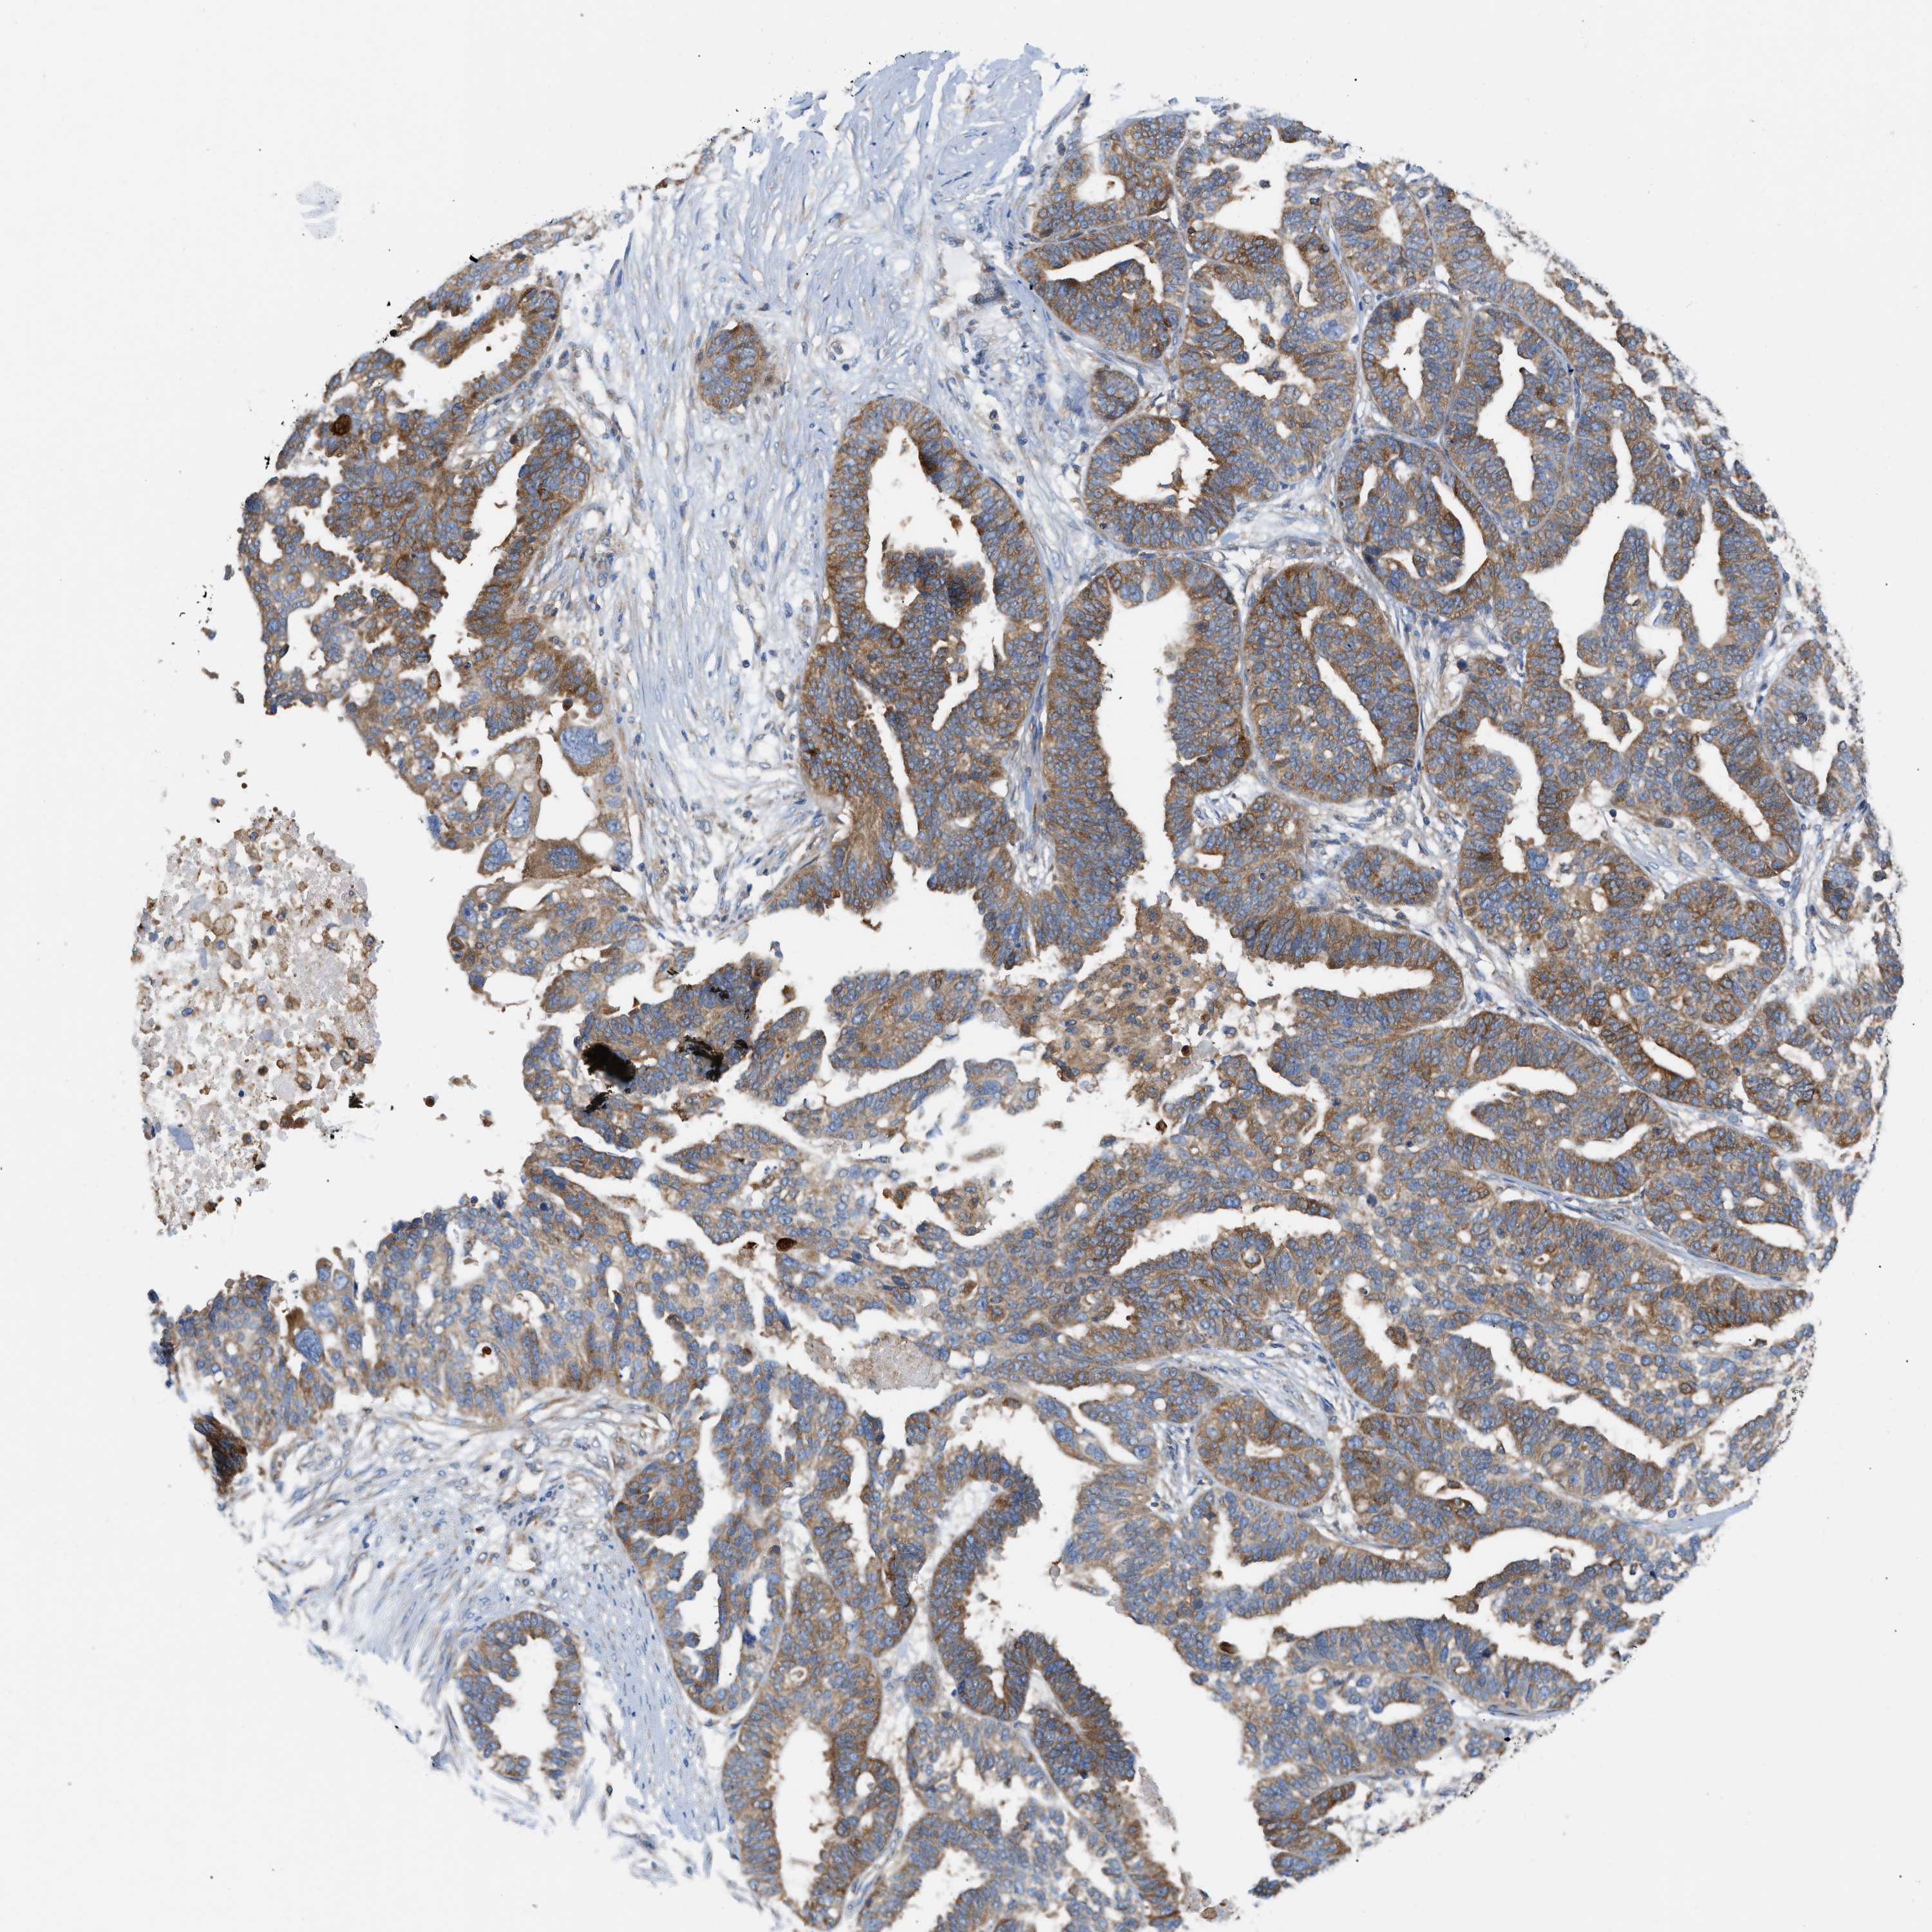

OVARIAN CANCER - Protein expressioni

A mouse-over function shows sample information and annotation data. Click on an image to view it in a full screen mode. Samples can be filtered based on level of antibody staining by selecting one or several of the following categories: high, medium, low and not detected. The assay and annotation is described here.

Note that samples used for immunohistochemistry by the Human Protein Atlas do not correspond to samples in the TCGA dataset.

Antibody stainingi

Antibody staining in the annotated cell types in the current human tissue is reported as not detected, low, medium, or high, based on conventional immunohistochemistry profiling in selected tissues. This score is based on the combination of the staining intensity and fraction of stained cells.

Each image is clickable and will lead to virtual microscopy that enables deeper exploration of all samples and also displays staining intensity scores, fraction scores and subcellular localization as well as patient and tissue information for each sample.

Antibody HPA016471

Staining

High

Medium

Low

Not detected

Intensity

Strong

Moderate

Weak

Negative

Quantity

>75%

75%-25%

<25%

None

Location

Nuclear

Cytoplasmic/membranous

Cytoplasmic/membranous,nuclear

Cystadenocarcinoma, serous, NOS

Carcinoma, endometroid

Cystadenocarcinoma, mucinous, NOS

Carcinoma, NOS